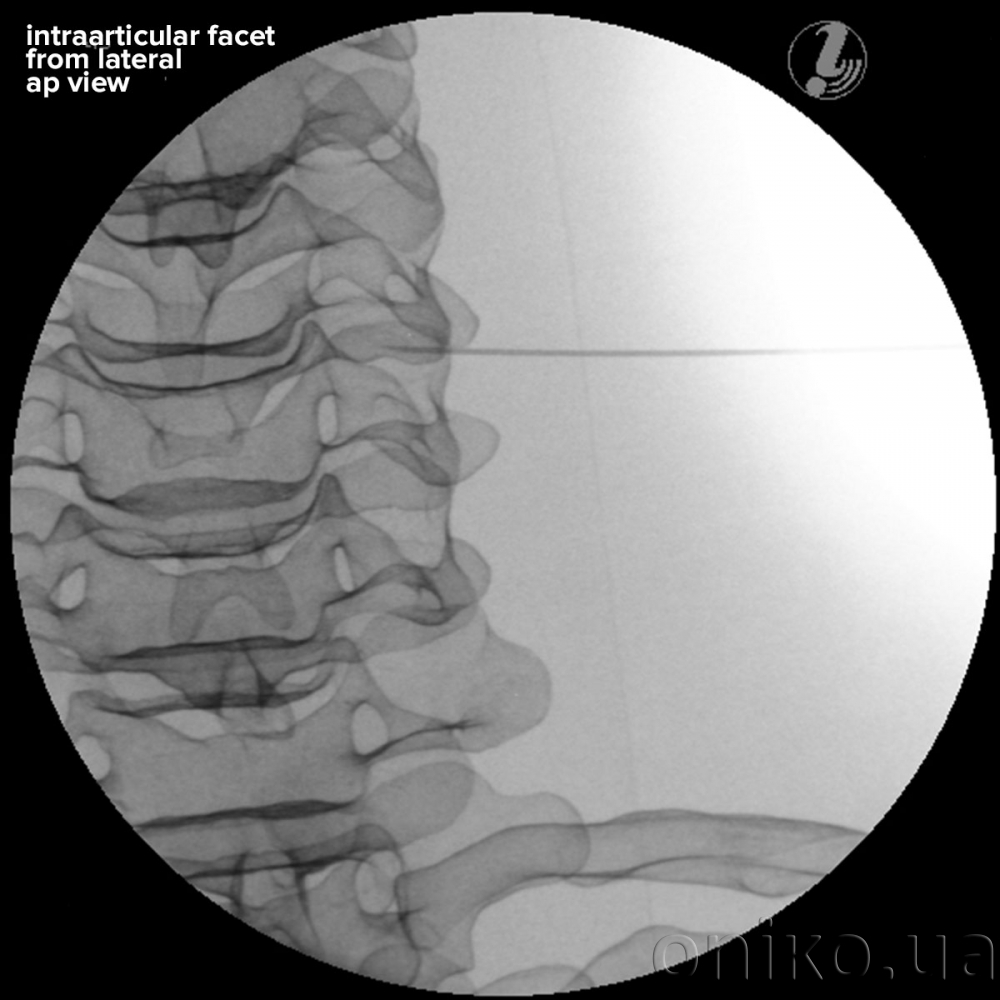

Simulátor pro procvičování injekčních dovedností pod vizuální kontrolou pro krční páteř

Simulátor pro procvičování injekčních dovedností pod vizuální kontrolou pro krční páteř umožňuje školitelům a posluchačům kurzů vypracovat prostorovou představu o pořadí postupu za účelem úspěšného lékařského zásahu na páteři. Budou se moci naučit korelovat anatomii páteře s vhodnými intervenčními analgetickými postupy, určením cílové tkáně a snadno poškozených struktur pomocí vizualizace a anatomického vyšetření a používat pokročilé techniky k zajištění bezpečnosti pacienta při provádění intervenčních postupů na páteři.

- Přírodní rentgenový kontrast pro realistické rentgenové snímky

- Anatomicky přesná kostní struktura

- Vizuálně definované anatomické orientační body